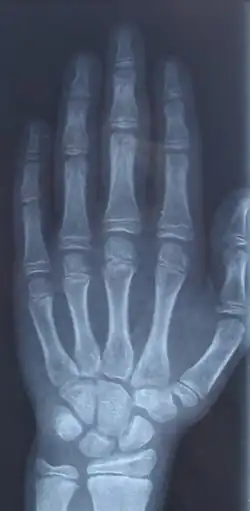

In der Kieferorthopädie (KFO) ist die Bestimmung des Beginns des pubertären Wachstumsschubs oft entscheidend, um den richtigen Zeitpunkt für den Beginn einer KFO-Therapie festzulegen. Handröntgenaufnahmen haben sich als zuverlässiges Instrument hierfür erwiesen. Hierfür existieren zwei gängige Methoden: Die erste stellt das sogenannte SMA-System (Skeletal Maturity Assessment) dar. Sie wurde von Fishman entwickelt, basierend auf der Beobachtung sechs anatomischer Punkte lokalisiert am Daumen, Mittelfinger, Pink und Radius.[7][8] Um die skelettale Reife von Patienten einschätzen zu können, benutzte Björk Reifeindikatoren, die für den kieferorthopädisch interessanten Altersbereich zwischen 9 und 16 Jahren typisch sind. Das Verhältnis von Dia- und Epiphysen der ersten, zweiten und dritten Phalanx sowie das Auftreten kleinerer Knochenstrukturen, beispielsweise. des Sesamoids, werden analysiert.[9][10] Daneben gibt es die Cervical Vertebral Maturation-Methode (CVM), mit der anhand von Röntgenaufnahmen der Halswirbel und der Halswirbelform das skelettale Alter bestimmt wird.[11]